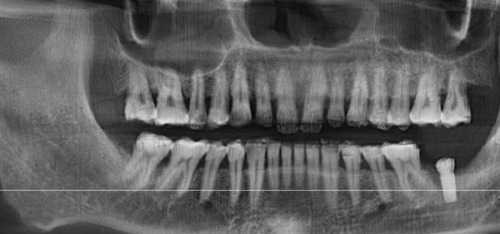

| 种植牙 | 2975元起 | 韩国仕诺康、奥齿泰、瑞士士卓曼等 | 含手术+种植体,不含牙冠 |